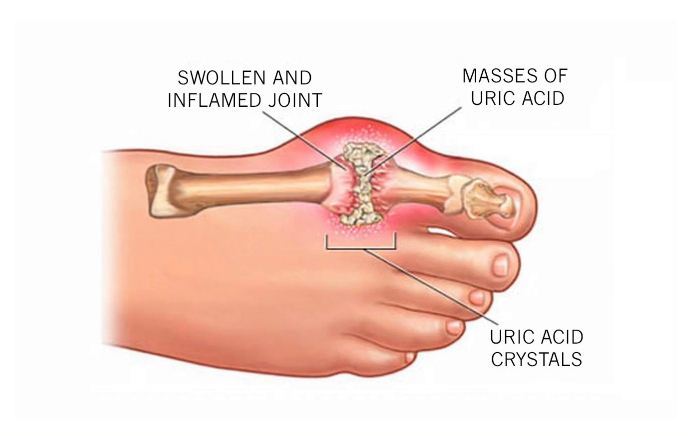

Common Foot & Ankle Disorders

Did you know the foot has 26 bones, 33 joints, 107 ligaments, 19 muscles, and numerous tendons? These parts all work together to allow the foot to move in a variety of ways while balancing your weight and propelling you forward or backward on even or uneven surfaces. It is no wonder that 75 percent of all Americans will experience foot problems at one point or another in their lifetimes.